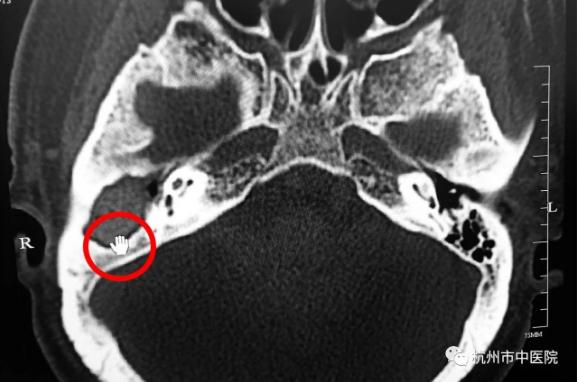

为明确诊断,梅医生又为徐大伯开出了螺旋CT检查,结果显示大伯的右侧外耳道骨壁、乳突区及听小骨骨质均被破坏、吸收,这些症状可能就是胆脂瘤破坏听小骨的传导功能而引发听力下降,又侵犯到面神经引起的面瘫的结果,如果再不及时进行干预,侵犯入脑就会引发生命危险。

ct片

“你先别哭呀,胆脂瘤并不是真正的肿瘤,可以手术除去的。”苏立众主任忙安慰泪眼婆娑的小林别紧张,并简单介绍此少见疾病的来龙去脉,然后开具了颞骨CT检查。

不出所料,颞骨CT检查显示小林左侧外耳道胆脂瘤,已挤压破坏左侧听骨链,且与左侧颈静脉及面神经管等重要结构关系密切,所以小林疼痛症状明显,左耳听力已有明显的下降。一切明了,小林如释重负。